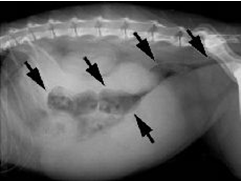

рис. 14а. Рентгеновский снимок суки с гнойными выделениями из влагалища и полидипсией/полиурией пиометра выглядит как мягкотканое изогнутое образование;

рис. 14b. Рентгеновский детальный снимок брюшной полости смазан и имеет гранулярную структуру в результате разрыва пиометры.

Причина: Типичная пиометра предположительно вызывается первичными инфекционными процессами. Примерно в конце эструса или начале проэструса бактерии поднимаются через открытую шейку матки в матку и вызывают воспаление. Повышение уровня прогестерона вызывает закрытие матки и одновременно уменьшает устойчивость эндометрия к бактериальным инфекциям. Количество бактерий в матке увеличивается, и возникает эндометрит с гиперсекрецией маточных желез. Постепенно матка наполняется гнойным секретом. Токсины из содержимого матки всасываются, и это приводит к токсемии. Острая фаза воспаления протекает клинически незаметно, фаза токсемии может проявляться различным образом. При анализе содержимого матки собак, страдающих пиометрой, обнаруживаются преимущественно неспецифические бактерии (главным образом, Е. coli, однако также и стафилококки, клебсиеллы, пастереллы и др, бактерии) (рис. 14a, 14b, 15).

Осложнения: В высшей степени редким осложнением при пиометре является гнойный перитонит, который может быть вызван спонтанным разрывом матки (рис. 14b), ятрогенным разрывом при пальпации или распространившимся через яйцевод заражением брюшной полости. Клинически эти случаи отличаются тяжелыми нарушениями общего состояния и наличием болезненной вздутости живота (рис. 19).